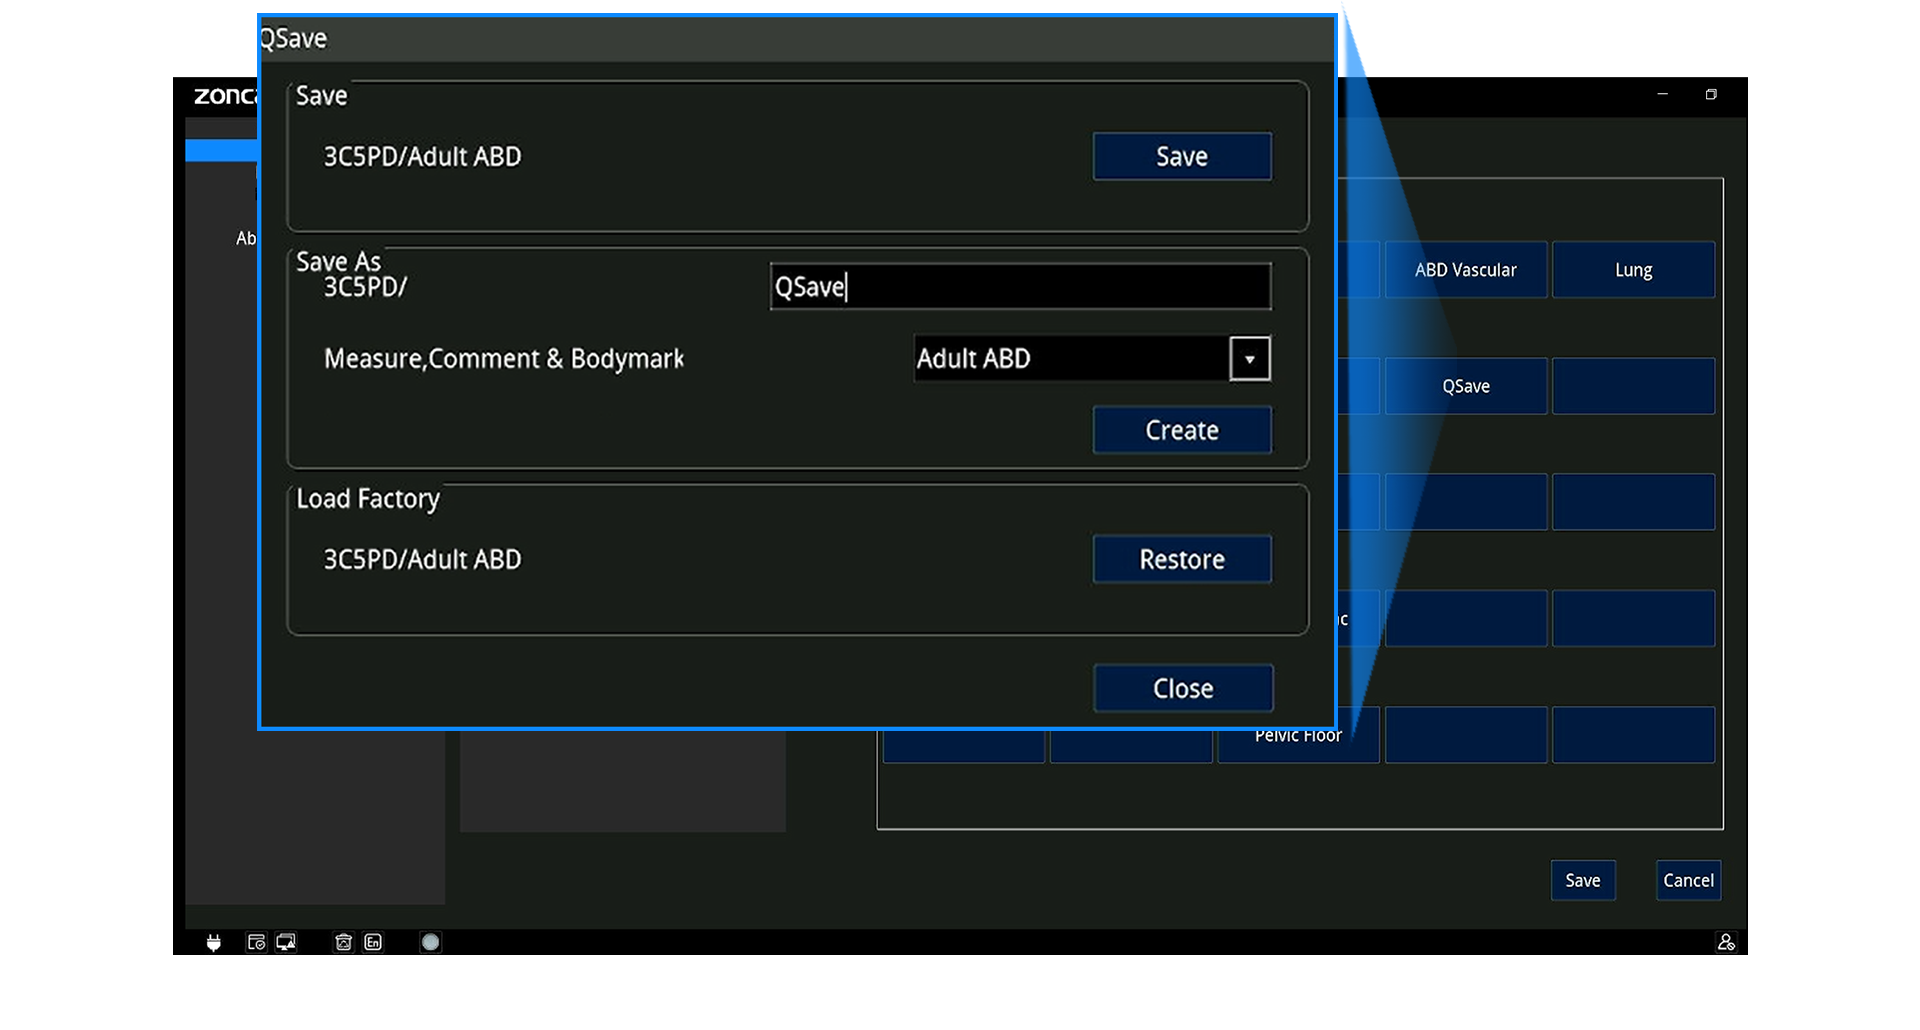

Panel ergonómico con trackball, TGC de 8 segmentos y teclas programables (Q1–Q4)

Almacenamiento, Datos y Conectividad

Formatos: RAW, DICOM, JPG, BMP, TIFF, AVI, MP4

DICOM 3.0 (Storage, Worklist, MPPS, Query/Retrieve, etc.)

Wi-Fi, Bluetooth, LAN, envío a PC

Teleconsulta remota, control inverso y docencia en vivo

Informes exportables a PDF (con opción de ocultar datos del paciente)